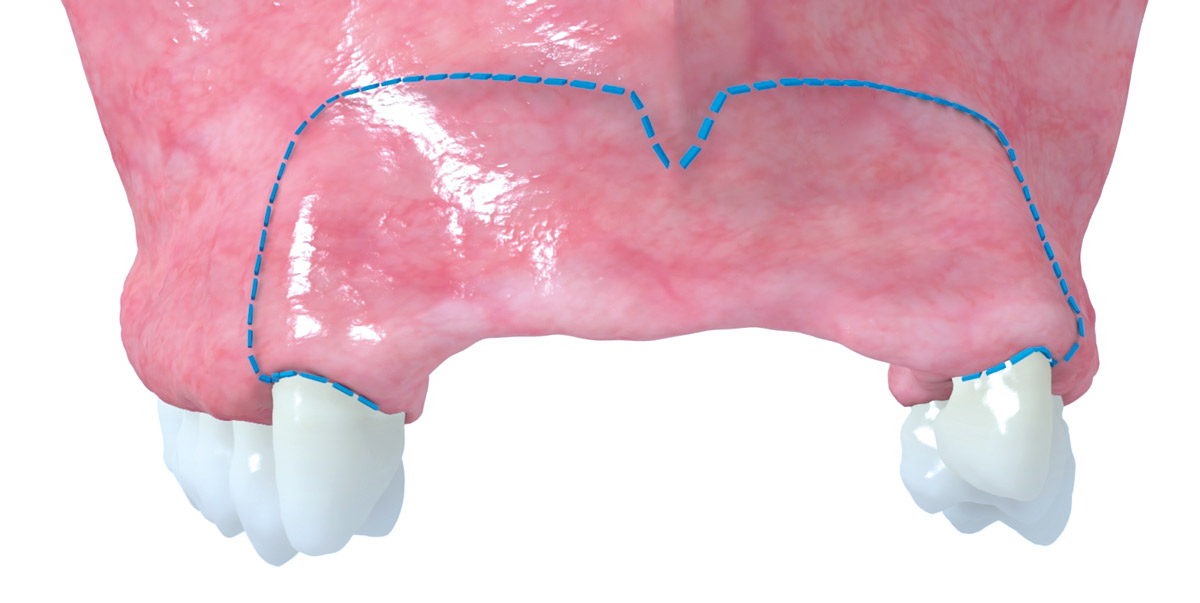

Lack of sufficient keratinized mucosa following extensive horizontal ridge augmentation